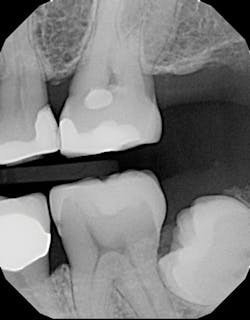

The difference in using this product over standard- or non-bulk-fill composites comes in the filling technique. The manufacturer states that you can predictably cure an increment of this composite up to 4 mm in depth. This assumes the light energy coming from your curing light is ideally positioned and is functioning properly (power intensity of 1000 mW/cm2 or greater). For carious lesions that are relatively small to moderate in size (figures 1a and 1b), this translates, in general, to being able to place one increment of composite that fills partway up the proximal box to the level of the contact and onto the occlusal pulpal floor (figure 2). The second increment could then be placed on top, which would fill the rest of the restoration.